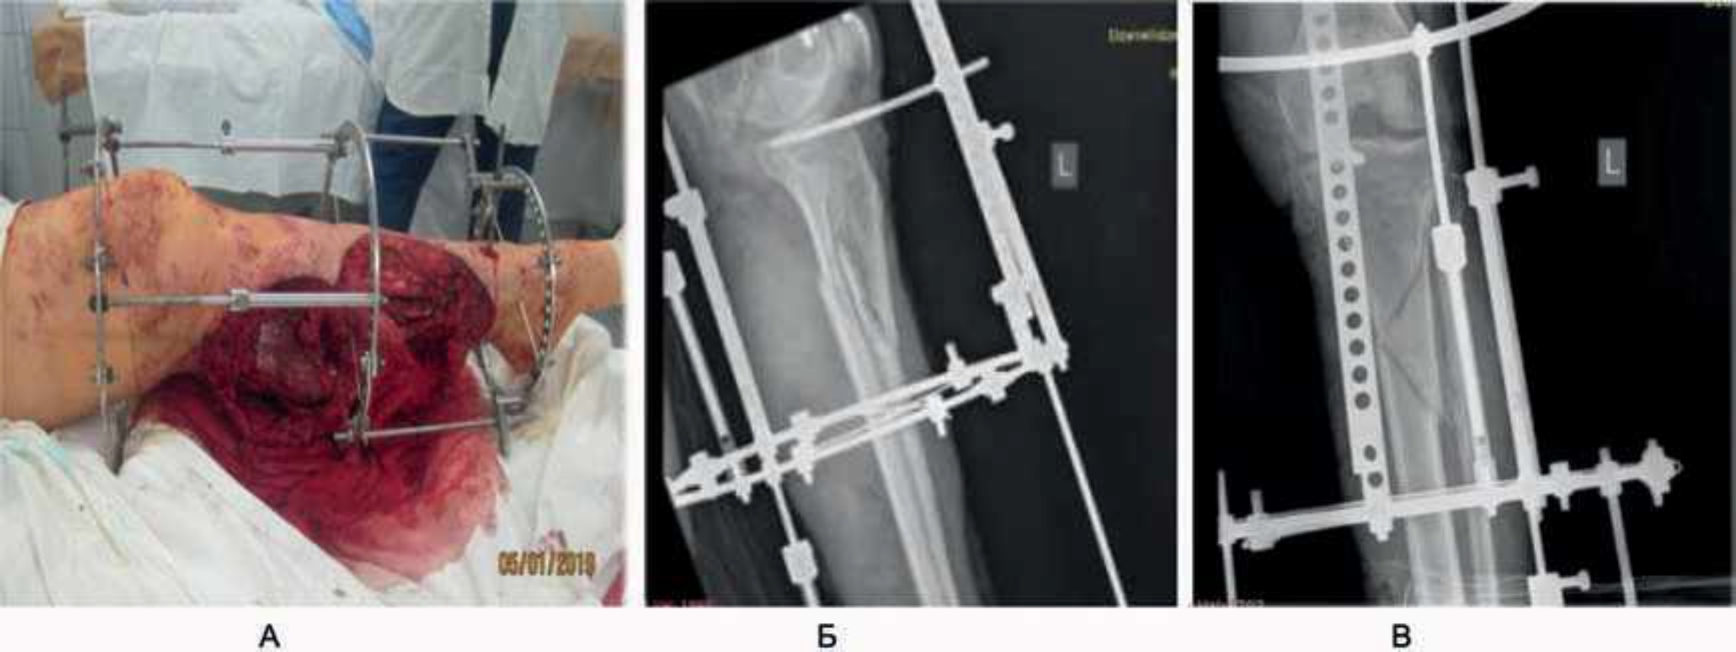

- Женщина, 29 лет, поступила в приемный покой после ДТП. Была сбита грузовым автомобилем. Время догоспитального этапа – 1 ч 23 мин. Диагноз при поступлении:

«Автомобильная травма. Открытый оскольчатый (по Густило IIIв) перелом верхней трети левой большеберцовой кости и нижней трети малоберцовой кости. Обширная открытая отслойка кожи левого бедра и голени. Закрытая ограниченная отслойка кожи по наружной поверхности правой голени» (рис. 10). Этапы хирургического лечения представлены на рис. 11, 12, результат восстановления кожного покрова – полное приживление трансплантата – на рис. 13. В течение 1 года пациентка носила компрессионное белье, занималась реабилитацией, в результате – восстановление движения в суставах левой нижней конечности в полном объеме (рис. 14).

Рис. 11. 1-е сутки: 1-й этап операции – металлоостеосинтез. Установка металлоконструкции (А), рентгеновский снимок, прямая (Б) и боковая проекция (В).